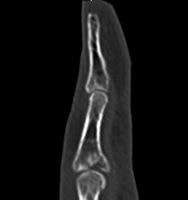

整形外科領域の手術において、骨を扱う際に必要なのがX線イメージです。当院では米ホロジック社製のフルオロスキャンを用いることにより、一般整形外科で用いる巨大なCアームでは見ることが困難な指骨の関節内骨折においても良好な整復操作を行うことを可能としています。